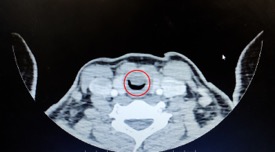

人活一口气,如果肿瘤把气管堵住了,人随时可能窒息而亡。前阵子,小欢在上体育课时,突然感到喘不上气来,情况十分严重,立刻被送到当地医院抢救。虽然“捡”回了一条命,女孩却被确诊为“气管肿瘤”,直径2公分的病灶已经把她的气管堵塞了90%!

病情危急,要立即治疗!胸外科气管亚专科姚烽主任接诊后,立即细致评估、制定治疗方案。切除肿瘤是救治女孩的唯一生路。气管重建手术是胸外科的高难度手术,手术技术、吻合重建方法都极为复杂,手术时间长,难度高、风险大,对麻醉、术后管理的要求也非常高。小欢的手术有两大难点,首先是肿瘤太大了,不仅要切干净,还要进行复杂的气管重建,才能保证她今后的呼吸通畅。更棘手的是,小欢的肿瘤位置太特殊了,距离发声的声门只有3毫米。术中如何保护好声带组织也非常关键,这直接影响了一个14岁女孩今后的生活质量。